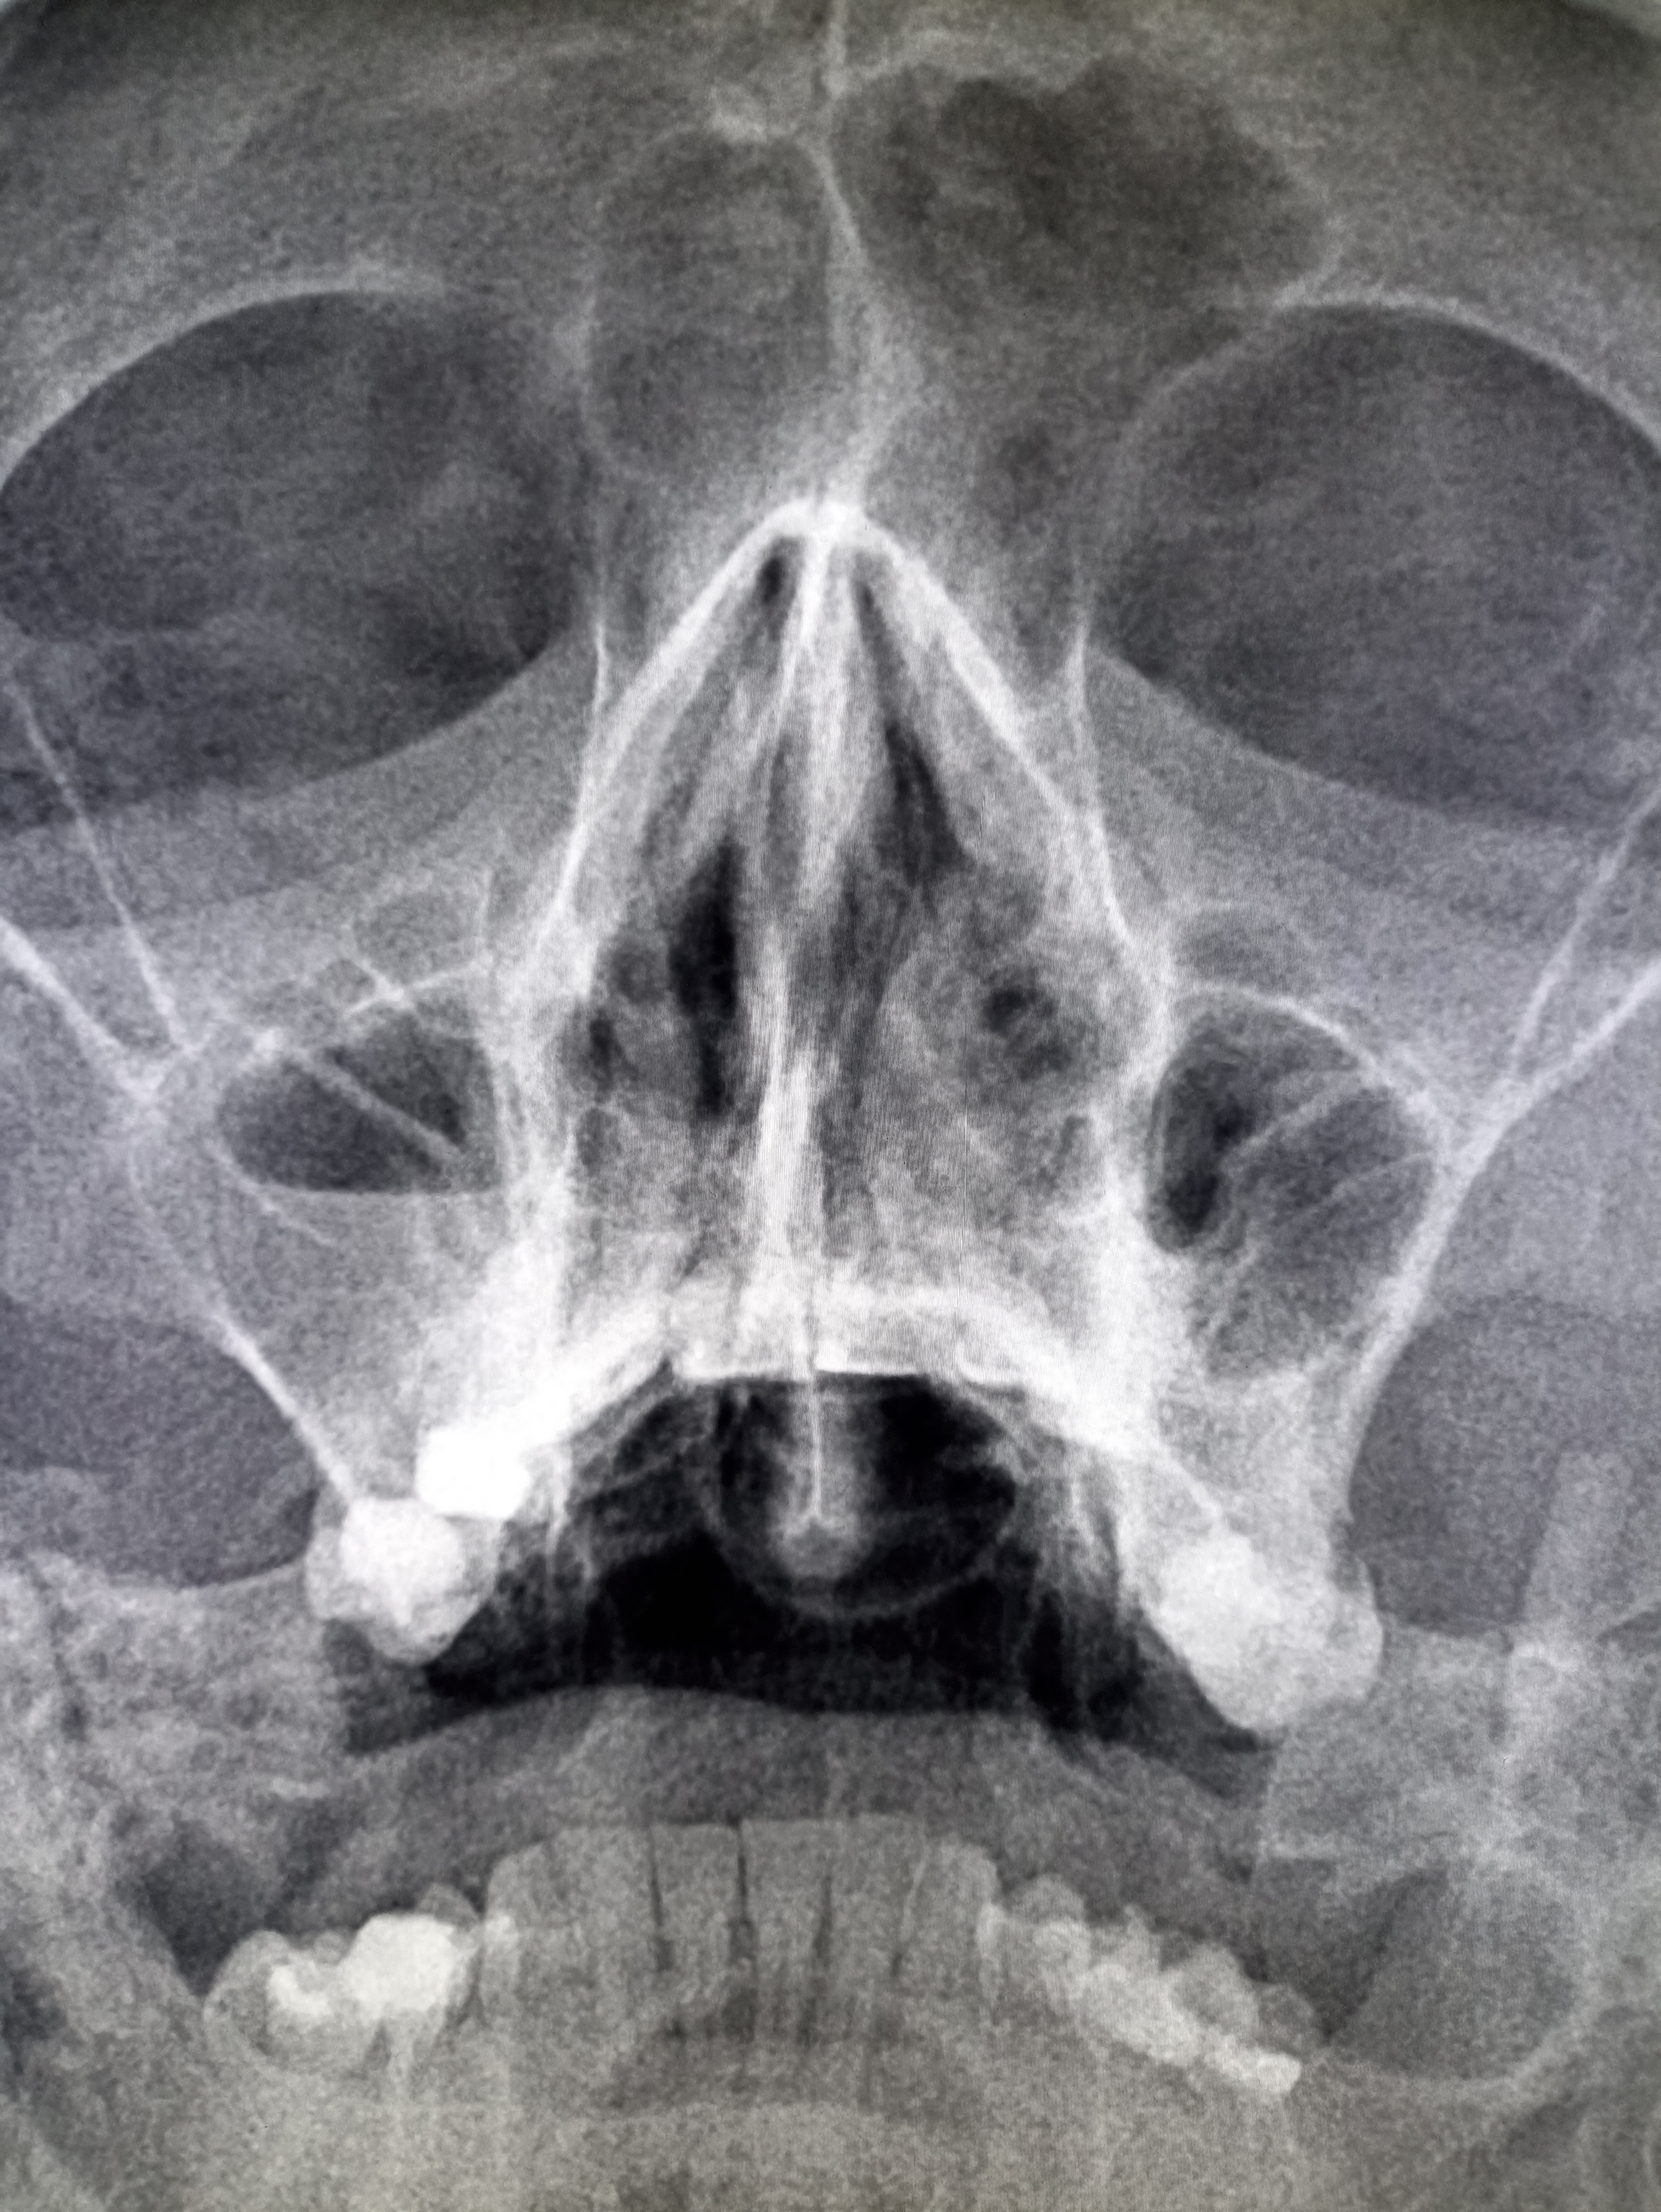

>>327481442

Аноним 09/12/25 Втр 12:26:10 #243 №327481575

А как с настроением у тебя дела, не замечал изменений в последние пару недель? Нет такой, знаешь, типа необычной для тебя активности, чтр вот прямо все успеваешь, такой продуктивный и с этого сам в ахуе с себя? Или, может, наоборот - все хуйня, ничего не радует? Какой лвл кстати?

Аноним 09/12/25 Втр 12:26:18 #244 №327481578

>>327481541

Сравни правую пазуху с прошлым снимком. Горизонтальный уровень видишь?

Аноним 09/12/25 Втр 12:29:01 #245 №327481666

>>327481578

Нихуя не увидел, я тупой соре

Аноним 09/12/25 Втр 12:31:36 #246 №327481750

IMG20251209143044.jpg

Желтым пазуха, красным жижка. Обвел тебе как мог у меня лапки!